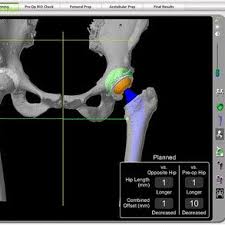

CT SCAN Each patient requires a pre-operative CT scan for the Mako TKA procedure. The Mako is a robotic arm-assisted surgery system transforming the way joint replacement surgery is performed.

Rdr2 thoroughbred black chestnut. Scan Location and Characteristics PositionLandmark Supine Feet First Topogram Scout Direction Cranio-Caudal. Cranio-maxillofacial CT Scanning Protocol Please keep in mind the following key points Please use a 3D scanning routine that provides high resolution images as would be suitable for image guided surgery stereotactic planning or other 3D applications. PDF 200004 CT Scanning Protocol Knee Arthoplasty GOMILCI 11A 2253 DESTRNIK ID za DDV. Rdr2 thoroughbred black chestnut. The initial step was determining the accuracy of the segmentation procedure. Final bone preparation trialing and implantation steps are executed with Triathlon Instruments as indicated in this technique. Knee 20 - 50mm interval spacing throughout the scan Axial slices 11 pitch using helical spiral scanning FOV. This scan must follow the protocol in the Mako Knee CT Scanning Protocol PN 200004.

This article aims to. This scan must follow the protocol in the Mako Knee CT Scanning Protocol PN 200004 INSTRUMENTATION The Mako TKA Instrumentation and Disposables. Introduction This surgical protocol describes the technique and instruments utilized to implant the Triathlon Knee during a Mako Total Knee procedure. MAKO TKA IMPLEMENTATION A. Mako Knee Instrumentation Mako Knee ArrayBalancing Kit. Cranio-maxillofacial CT Scanning Protocol Please keep in mind the following key points Please use a 3D scanning routine that provides high resolution images as would be suitable for image guided surgery stereotactic planning or other 3D applications. In the operating room your surgeon guides Makos robotic arm to remove the arthritic bone and cartilage from the knee.